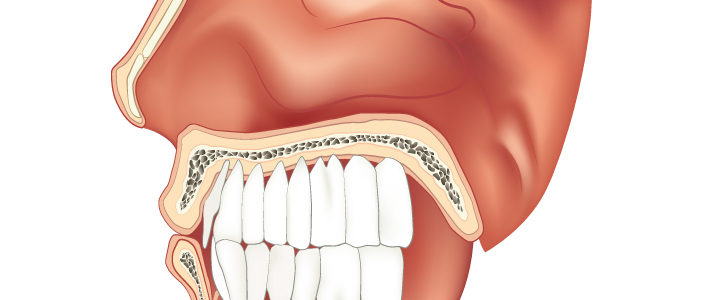

Cosa rischi se non rimpiazzi subito un dente perso?

Molti pazienti ci confidano di avere la bocca in pessime condizioni, ma di non avere il coraggio di affrontare il problema.

Così, accade che la cosa più semplice da fare sia tenersi tutto dentro e far finta che il problema non esista. In realtà, se continui a rimandare la prima visita dal dentista rischi di avere complicanze che renderanno le cure molto più complicate e costose.